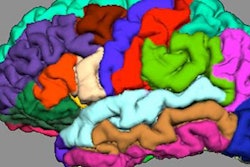

MRI shows activity (red and yellow areas) in the caudate region of the brain, which is affected in people with psychosis. Image courtesy of King's College London.All participants underwent MRI scans while performing a memory task to engage three regions of the brain involved in psychosis.

Among those at risk for psychosis, the subjects who were given cannabidiol showed less-severe abnormal brain activity than those who received a placebo, suggesting that cannabidiol can help readjust brain activity to normal levels.